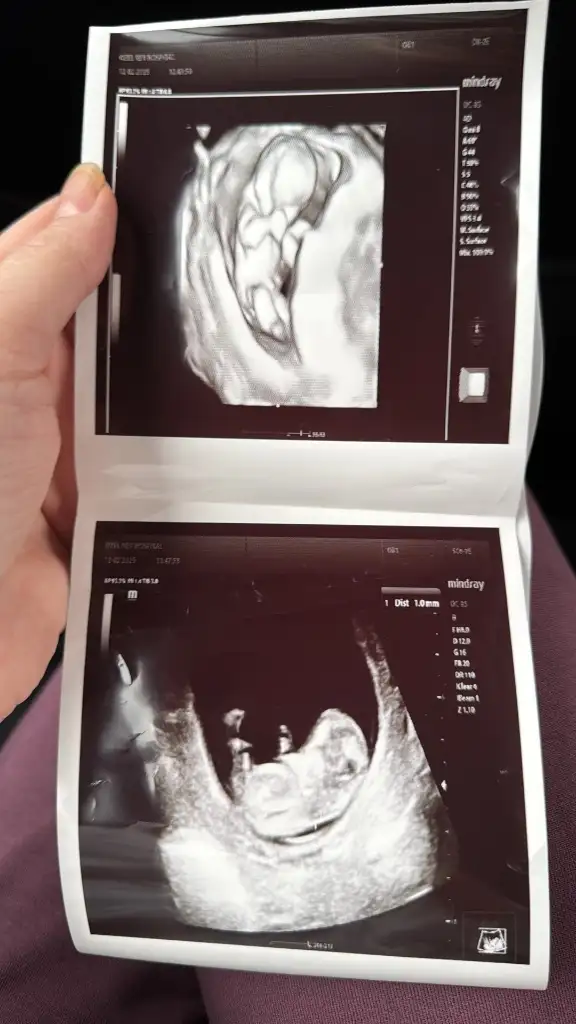

Selam cnm ayy nasılsın maşallah bebiş büyümüş ya cinsiyeti belli oldumu 🥰

Selam tatlım. Çok iyiyim mide bulantılarım oluyor inanılmaz derece de ilaç kullanıyorum. 11+2 haftada %70-80 kıza benziyor demişti. Dün gittik 12+6 tahmin de bile bulunmadı doktorum. Çok üzüldüm. :( sizlerin nasıl gidiyor

İyi bizde işte hala bekliyoruz sabırla kesenin fotosu varmı bakayım bende

En yakın zaman da inşallah güzel haberi alırsın kuzucum. En başından beri kız hissediyorum 🥹 sabırsızlanmaya başladım artık

Eklentiler

• 2C458021-4C67-4FBE-9065-1B957876F74C.webp

2C458021-4C67-4FBE-9065-1B957876F74C.webp

30,2 KB · Görüntüleme: 61

• FE751E51-DCCF-4A54-A51C-5E43B433A29F.webp

FE751E51-DCCF-4A54-A51C-5E43B433A29F.webp

27,8 KB · Görüntüleme: 64

• IMG_0593.webp

IMG_0593.webp

39,4 KB · Görüntüleme: 63